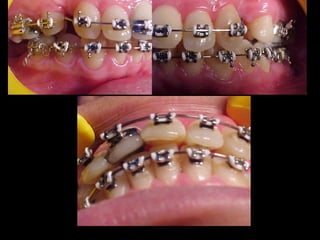

Eliminación de rotaciones.

Corrección de las discrepancias de longitud de arco.

Posición de los incisivos y molares por medio del

torque adecuado.

Llevar cualquier otra alineación en el arco.

Evita el potencial de recidiva

Aumenta la velocidad y eficacia del tratamiento

Eliminación de rotaciones. Correcciónde las discrepancias de longitud de arco. Posición de los incisivos y molares por medio del torque adecuado. Llevar cualquier otra alineación en el arco. Eliminación de rotaciones. Corrección de las discrepancias de longitud de arco. Posición de los incisivos y molares por medio del torque adecuado. Llevar cualquier otra alineación en el arco.

Evita el potencialde recidiva Aumenta la velocidad y eficacia del tratamiento